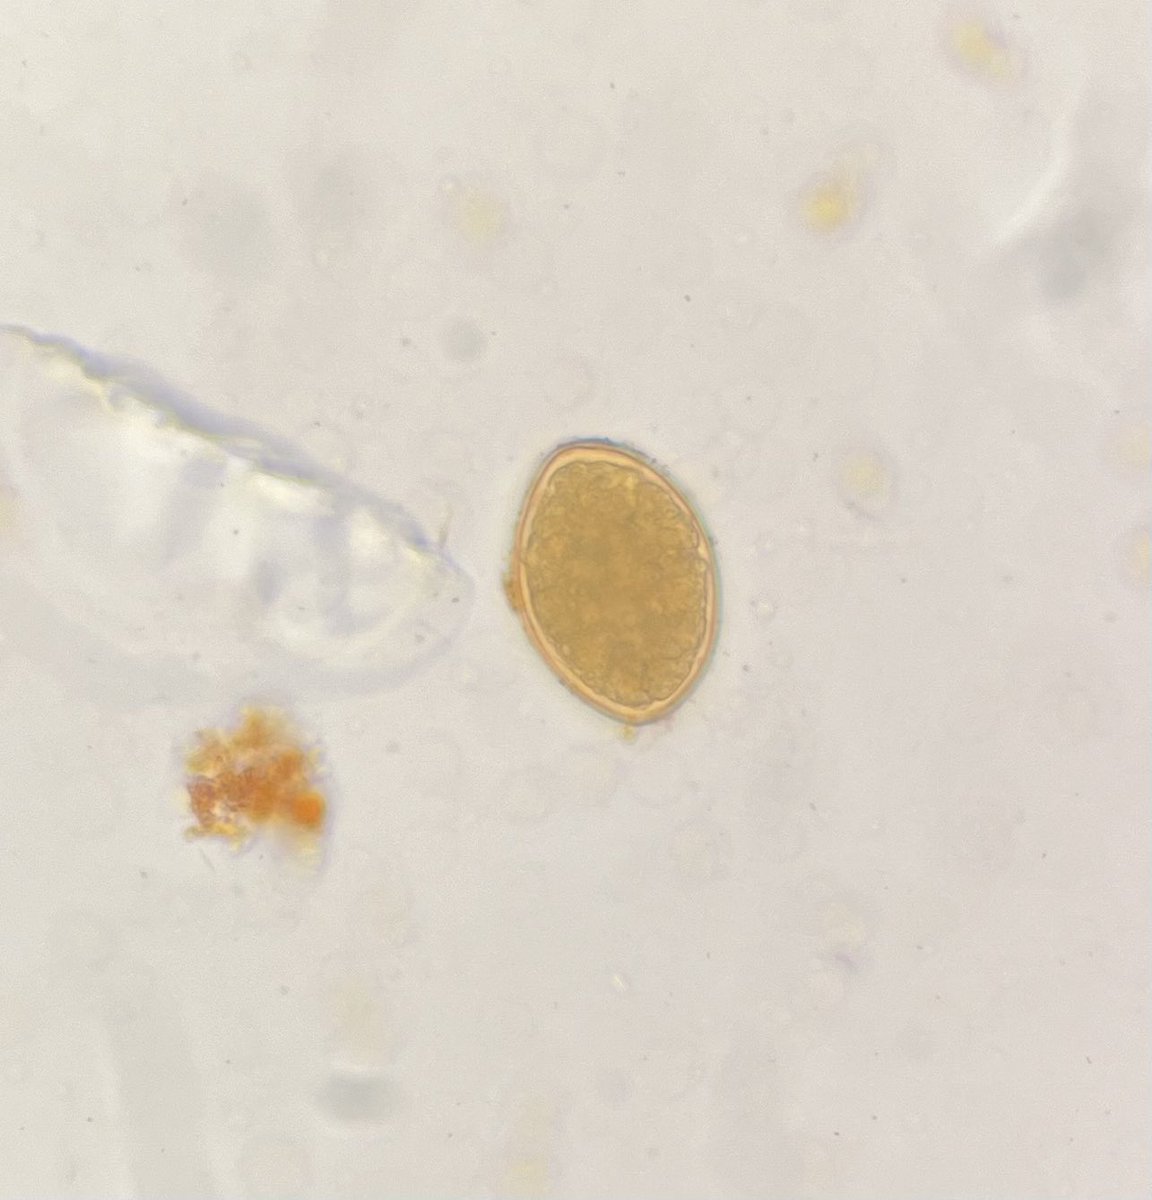

Parasitology lab today! Students got to see arthropods, blood parasites, cestodes, trematodes, nematodes, amoebas, flagellates, coccidia and microsporidias! #Lab4Life #IamASCLS

Hey @MLSatLoyola students, we just covered this on Monday. Which vitamin deficiency do you suspect?

Peripheral blood smear of a vegan patient with complaints of fatigue. What is the pathlogyโ“๏ธ #MedTwitter #MedEd #MedX